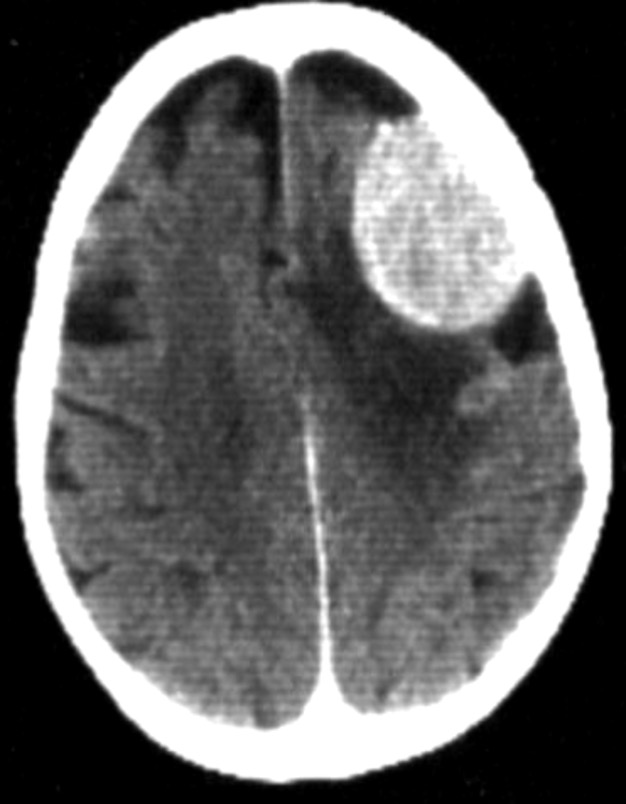

- Definition - well defined

- Shape - Oval shape

- site - Fronto-parietal

- Size - 4x3 cm

- Enhancement - Homogenous

- Oedema

- Sulci,

- ventricles Normal